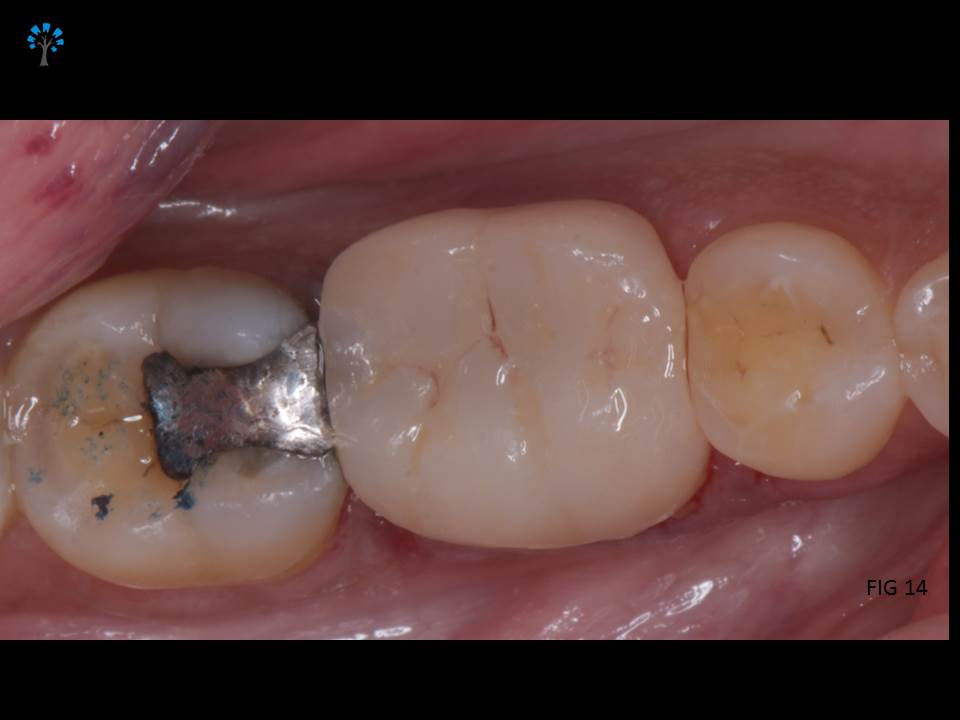

Crown Preparation was done and a digital scan (fig 11) for an impression was obtained.

Monolithic EMAX crown was fabricated (KATARA DENTAL, PUNE) and bonded.(Fig 10 -12)